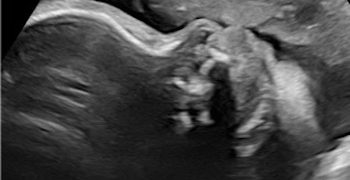

Casi del Mese di Maggio 2022

Cari soci, finalmente online le soluzioni dei casi di Maggio!!! Caso 1 Scarica il File Caso 2 [pdf-embedder url="https://www.sieog.it/wp-content/uploads/2022/05/caso-clinico-maggio-2-risposta.pdf" title="caso...